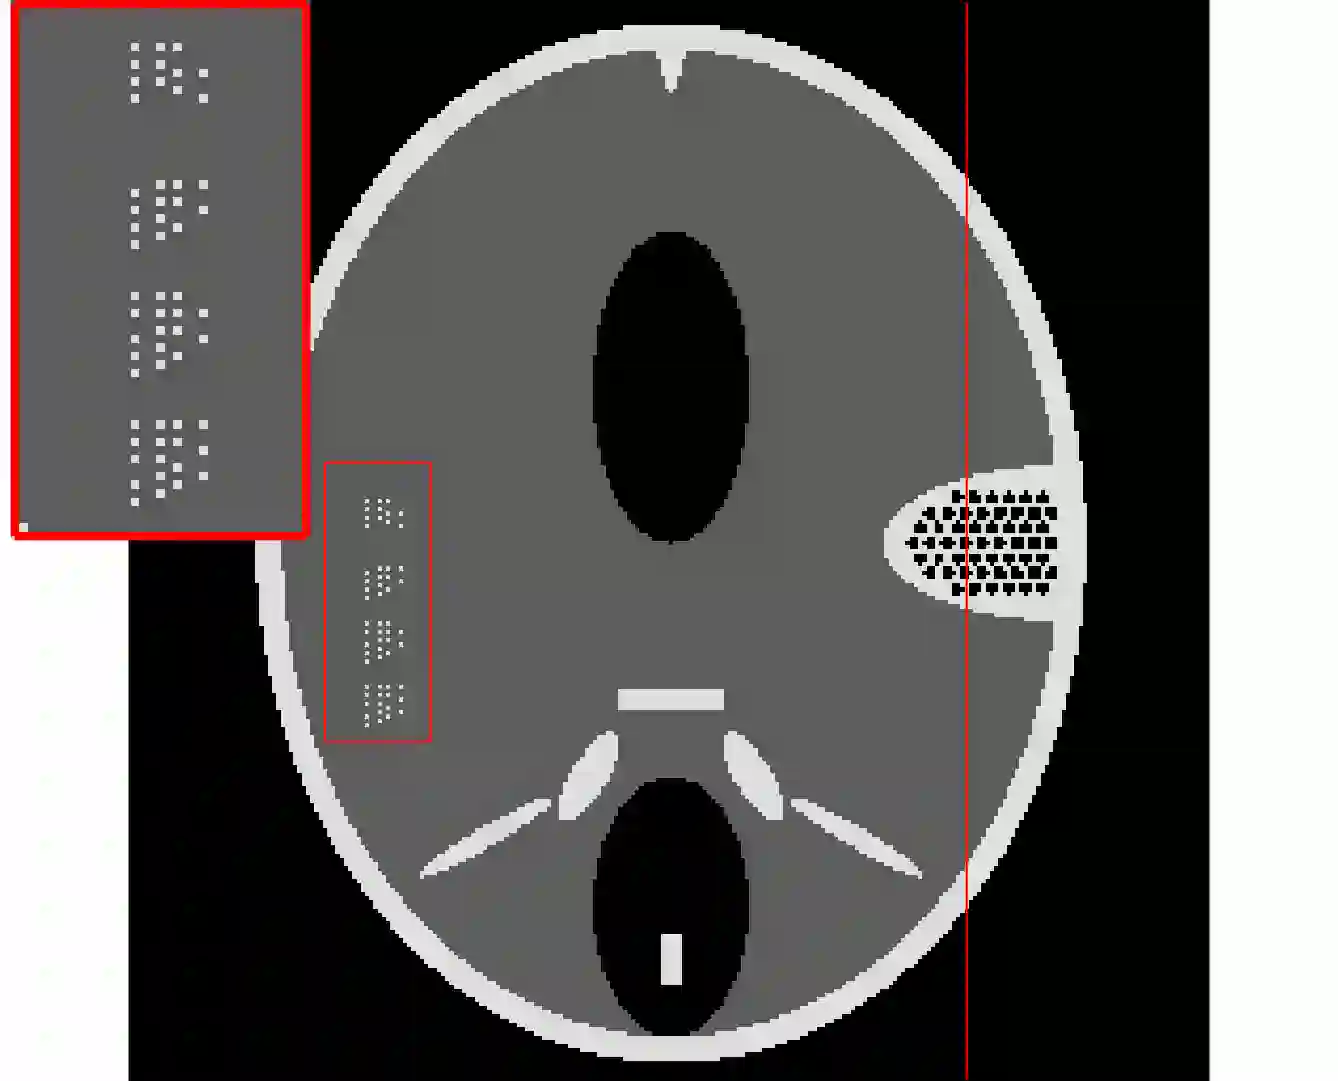

In the classic sparsity-driven problems, the fundamental L-1 penalty method has been shown to have good performance in reconstructing signals for a wide range of problems. However this performance relies on a good choice of penalty weight which is often found from empirical experiments. We propose an algorithm called the Laplacian variational automatic relevance determination (Lap-VARD) that takes this penalty weight as a parameter of a prior Laplace distribution. Optimization of this parameter using an automatic relevance determination framework results in a balance between the sparsity and accuracy of signal reconstruction. Our algorithm is implemented in a transmission tomography model with sparsity constraint in wavelet domain.